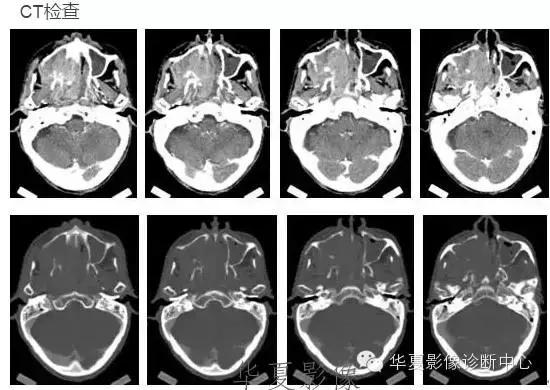

中枢神经系统内原发性黑色素瘤少见, 因脑和脊髓的软脑( 脊) 膜及蛛网膜上含有黑色素细胞, 黑色素可发生于软脑( 脊) 膜的任何部位,故其发生部位常位于脑( 脊髓) 表面, 沿软脑膜生长; 而继发性黑色素瘤同一般转移性肿瘤, 常位于灰白质交界区。

影像表现:常表现为短 T1 高信号, 短T2WI 低信号,又因为黑色素瘤是富血管性肿瘤, 增强扫描常表现为明显强化。

★但少数肿瘤也不具备上述典型信号特征,主要原因是肿瘤内黑色素量多少影响。只有当黑色素瘤中黑色素细胞超过一定含量( ﹥ 10% ) 时, 才会出现黑色素瘤的典型MRI表现; 不典型的黑色素瘤因其黑色素含量较少,不足以缩短T1、T2弛豫时间,而表现为长T1低信号、长T2高信号。

依据黑色素瘤的不同 MRI 影像表现将其分为 4 种类型: ( 1) 黑色素型。该黑色素瘤因含有丰富的黑色素颗粒, MRI表现较典型,即短 T1 高信号,短 T2 低信号。( 2) 无黑色素型。因该类黑色素瘤不含黑色素颗粒或含量较低,MRI 表现为长 T1 低信号,长 T2 高信号; ( 3) 混合型。黑色素型和非黑色素型两者的混合; ( 4) 出血型。表现为血肿不同时期的信号特征, 该黑色素瘤 MRI增强扫描表现为不均匀环状或弥漫性强化